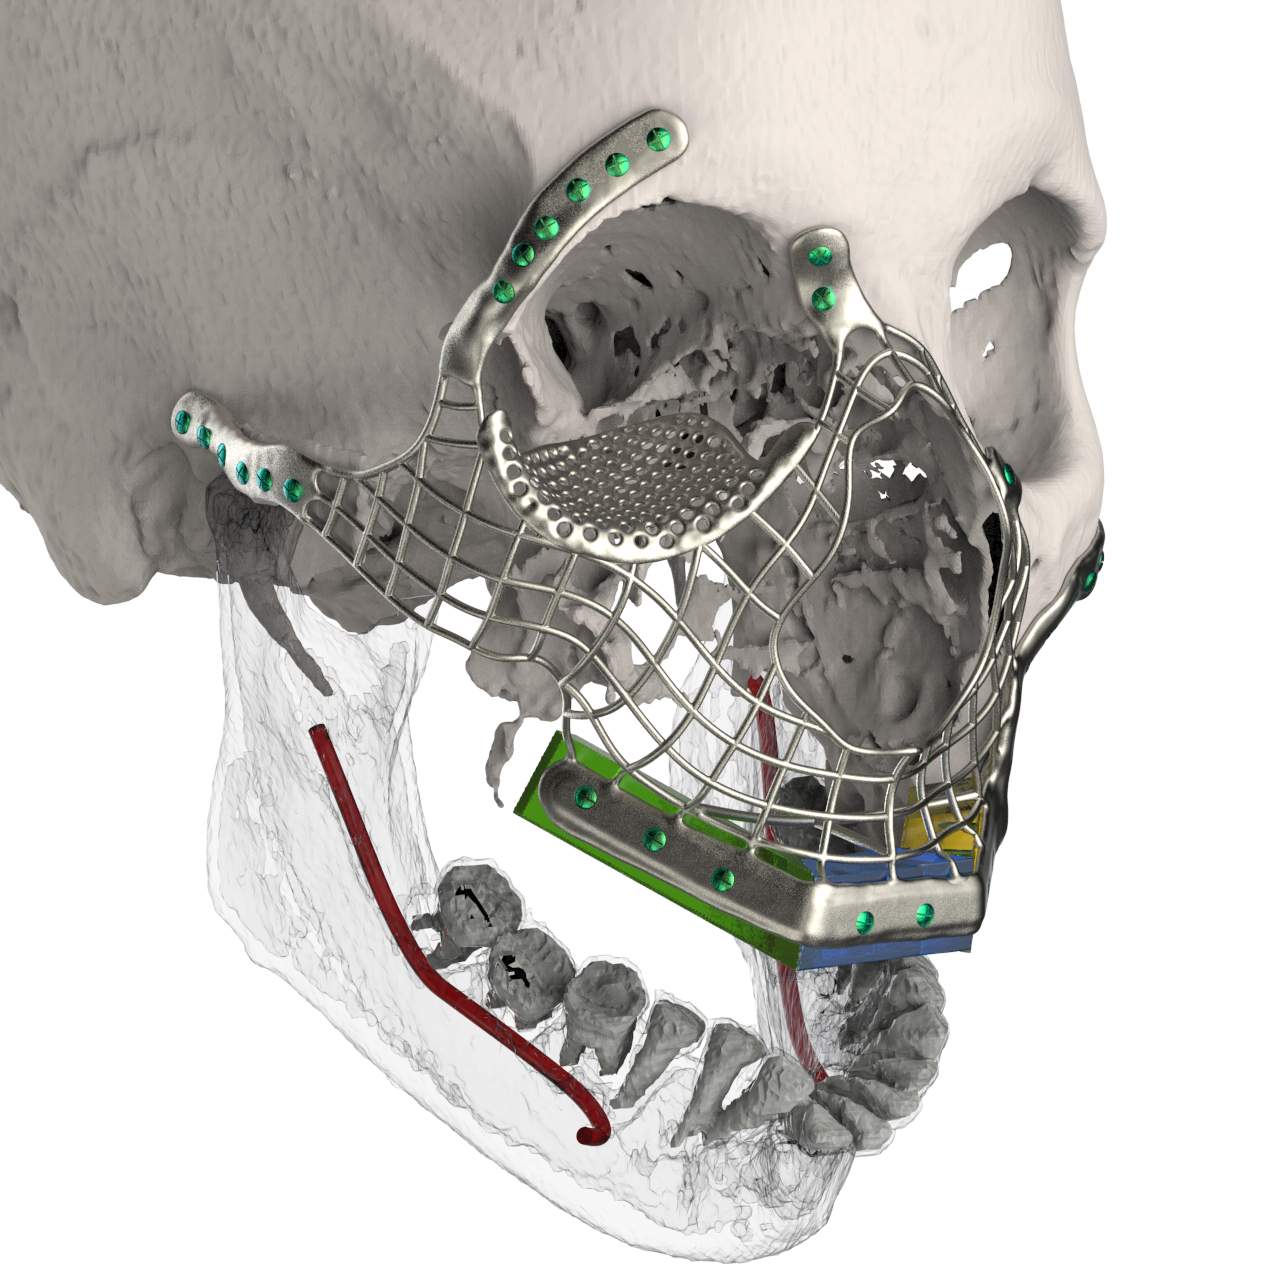

Patient-specific equipment and systems

Patient-specific equipment (such as hearing aids) and implants (such as artificial limbs, cranial plates, and even heart valves) are increasingly turning to 3D printing for rapid modification and accelerated development.

There are design advantages too: 3D printed silicone heart valves have the perfect match that rigid, commonly designed heart valves simply can’t. For implants such as titanium artificial joints or cranial plates, the services of 3D printing companies can produce intricate and porous surfaces that make patients’ bodies less likely to resist implants.

Customized Surgical Instruments

Precision and quality are everything in the operating room. The particular complexity of each operation cannot be underestimated: the anatomy of each patient is different from that of each surgeon’s hands. When thorough control is required, why should surgeons limit themselves to one-size-fits-all surgical instruments?

The 3D printing service offers a cost-effective and timely option for developing customized surgical instruments based on the needs of each surgeon and each operation. These instruments are made of sterilizable and biocompatible plastics and metals. Therefore, the tools can be disposable or reusable.

Surgical instruments tailored to the size and shape of each surgeon’s hands, as well as additional customization for each application, can significantly increase accuracy and productivity. In addition, detailed surgical guides for each patient can improve accuracy while reducing time in the operating room by minimizing the need to consult diagrams and wizards.